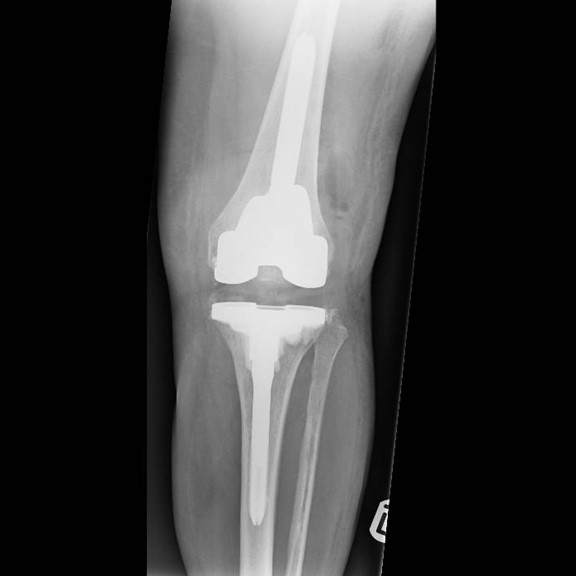

Generally, bone cement is used to fix a total knee replacement to the bone, in some cases where an uncemented knee replacement is used the host bone grows onto the implant. If this interface between the bone and the cement or the bone and the implant (in an uncemented knee) fails then the implant will loosen and will result in progressive pain. Usually loosening occurs many years after surgery, if it occurs early on it is often due to a technical problem during the implantation surgery.

Another cause of loosening can be a wearing out of the plastic insert that sits between the metal implants of the femur and tibia. These wear particles that are generated can cause quite extensive bone loss around the implant and this significantly increases the complexity of the surgery.

It is therefore important that your surgeon has a range of options available to him to reconstruct the knee after a failed knee replacement. This may include advanced surgical approaches, use of complex revision implants including custom made implants, use of bone graft or trabecular metal implants to reconstitute lost bone.

When a total knee replacement is performed, the bone cuts have to be performed correctly, the implants have to be inserted in the right manner and the knee must be balanced by the end of the operation. Failure to achieve this will lead to problems in the long-term. If the knee is too tight, it will result in stiffness and difficulty in achieving a full range of motion in the knee. If it is too loose it will cause instability and the knee will give way.